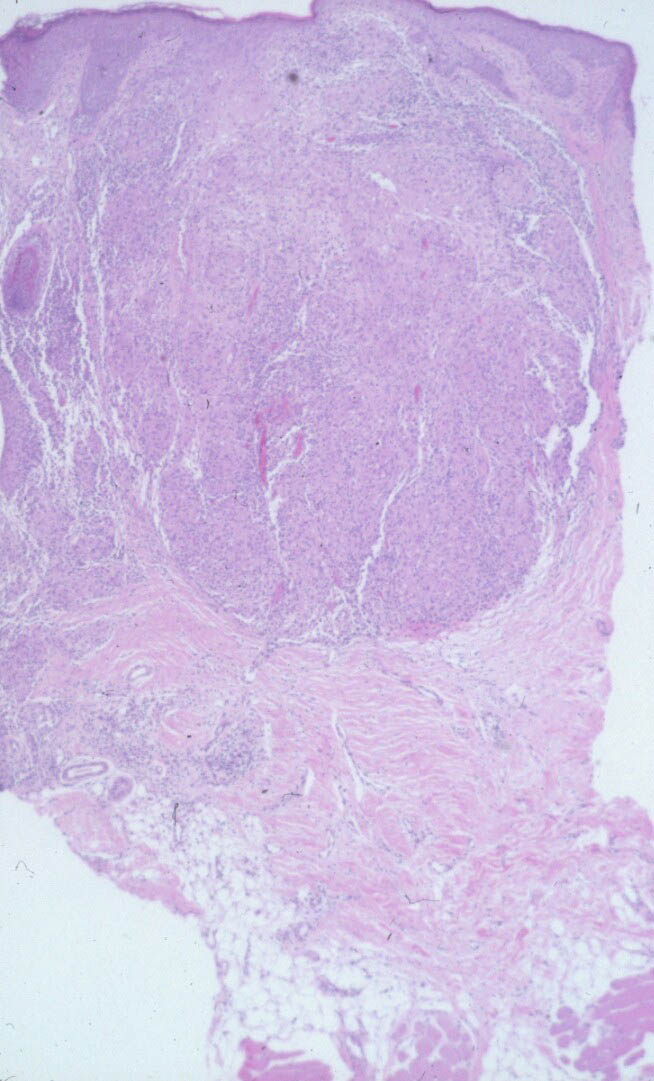

Like lesions in other organs, the cutaneous lesions of chronic, persistent sarcoidosis are characterized by the presence of circumscribed collections of epithelioid histiocytes-so-called epithelioid cell tubercles-which show little or no necrosis .

The papules, plaques, and lupus pernio-type lesions show variously sized aggregates of epithelioid cells scattered irregularly through the dermis with occasional extension into the subcutis (. In the erythrodermic form, the infiltrate shows small granulomas in the upper dermis intermingled with numerous lymphocytes

hypopigmented sarcoid may reveal granulomas, which may have a perineural component or fail to reveal granulomas . In subcutaneous nodules, larger epithelioid cell tubercles lie in the subcutaneous fat .

eosinophilic staining is found in the center of some of the granulomas . A reticulum stain of sarcoid reveals a network of reticulum fibers surrounding and permeating the epithelioid cell granulomas. If the granulomas of sarcoidosis involute, fibrosis extends from the periphery toward the center, with gradual disappearance of the epithelioid cells . Fibrosis, however, is minimal to absent in most examples of sarcoidosis, with the exception of the morpheaform variant, where it is prominent {191}. Other features that may sometimes be seen include elastophagocytosis, increased dermal mucin, and lichenoid inflammation .